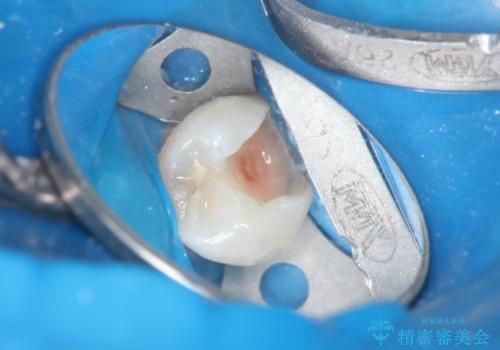

顕微鏡下で丁寧に虫歯を取り除き、セラミックインレーによる修復治療を行いました。

虫歯が大きく広がっていましたが、顕微鏡を使って慎重に治療を行うことで、神経をとってしまうことなく治療することができます。